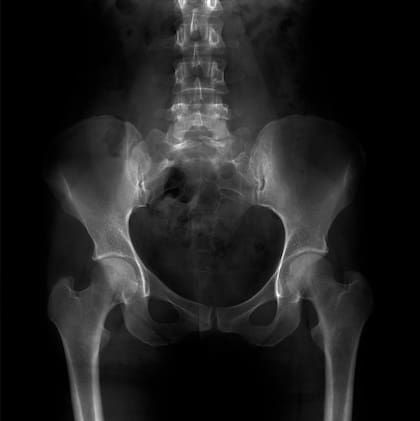

Una de las diferencias más evidentes entre nosotros y muchos parientes primates es que no tenemos cola. La pérdida de la cola se produjo hace unos 25 millones de años (a modo de comparación, nuestro antepasado común con los chimpancés fue hace unos 6 millones de años). Aún conservamos el coxis como resabio evolutivo de este ancestro portador de cola.

Pero el equipo observó otra cosa extraña. Si se crea un ratón con sólo la forma del gen TBXT con la sección excluida, pueden desarrollar una afección muy parecida a la espina bífida humana (cuando la columna vertebral y la médula espinal no se desarrollan correctamente en el útero, causando un hueco en la columna vertebral).

Anteriormente se habían relacionado con esta enfermedad mutaciones en el TBXT humano. Y hay que observar que otros ratones también presentaban diferentes defectos en la columna vertebral y la médula espinal.

El equipo sugiere que, al igual que el coxis es una secuela evolutiva de la falta de cola que todos tenemos, la espina bífida puede ser una secuela rara de la alteración del gen que sustenta nuestra falta de cola.

No tener cola, sugieren, era una gran ventaja, por lo que un aumento de la incidencia de la espina bífida seguía mereciendo la pena. Este puede ser el caso de muchas enfermedades genéticas y del desarrollo: son un subproducto ocasional de alguna mutación que, en conjunto, nos ayudó.